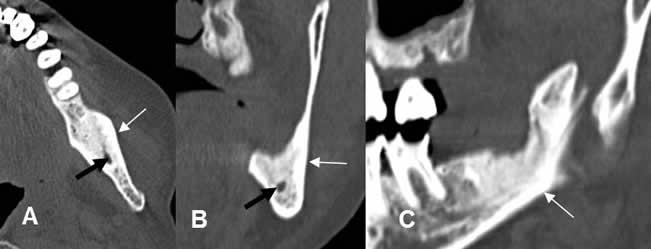

Fig 73 A. Tumor.

A: TAC axial, B: TAC reconstrucción coronal y C: TAC reconstrucción sagital. Alteración en la densidad del ángulo de la mandíbula, por lesión heterogenea, lítica/blástica, que corresponde a metástasis de tumor de mama.

Fig 73 B. Seguimiento de tumor.

A: TAC axial, B: TAC reconstrucción coronal y C: TAC reconstrucción sagital.

Aumento de la densidad en el ángulo de la mandíbula, secundario a cambios post-radioterapia. (Flechas delgadas).Canal dental, en el centro de la imagen. (Flecha negra).